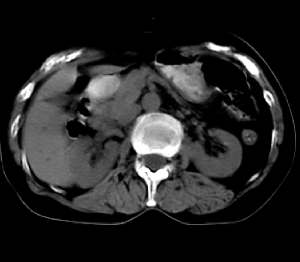

患者无任何不适及阳性体征,超声体检时发现,未做增强扫描。囊影密度均匀,ct值略高于水,囊影壁薄光滑,囊内密度均一。定性诊断不难,应是个囊肿。请大家做个定位诊断

1.无临床症状。2.小网膜囊组织受压推移。3.肝内胆管正常。纵上3点,考虑小网膜或肠系膜囊肿可能性大,最好mpvr多平面重建。

病灶上部层面与肝脏交界清楚但不太截然,下部层面与肝之间可见线状高密度带,考虑由囊块压迫肝实质形成,考虑caroli氏病,其次考虑左肝囊肿向下向肝外生长,另外其他来源囊肿及消化道重复畸形不排除